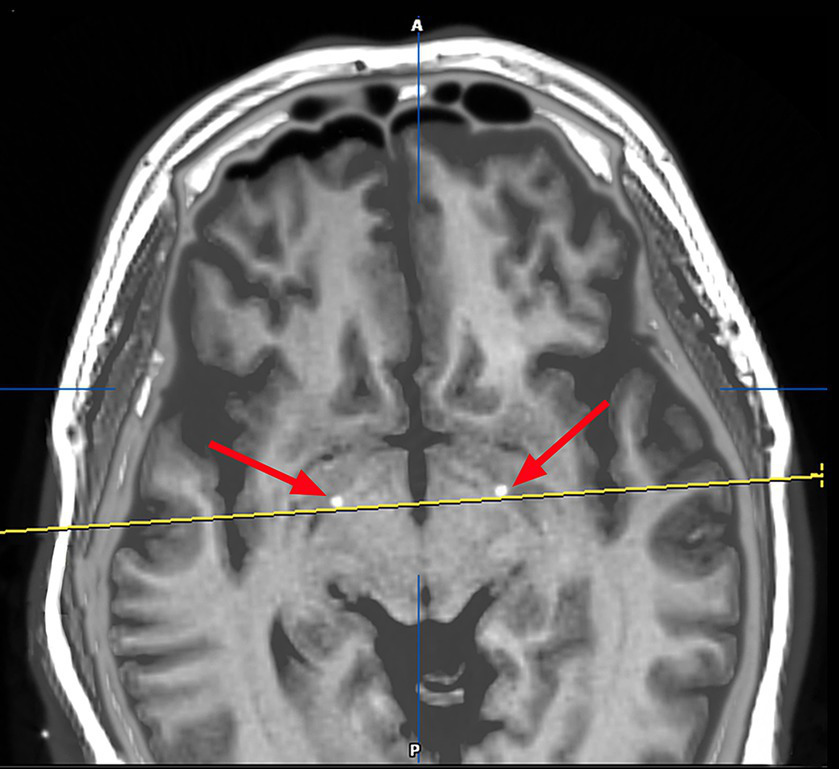

Figure 3

Image after fusion of preoperative MR plan and postoperative CT and it is a postoperative image fusion, suggesting that the stimulation electrode is precisely located in the GPI nucleus.